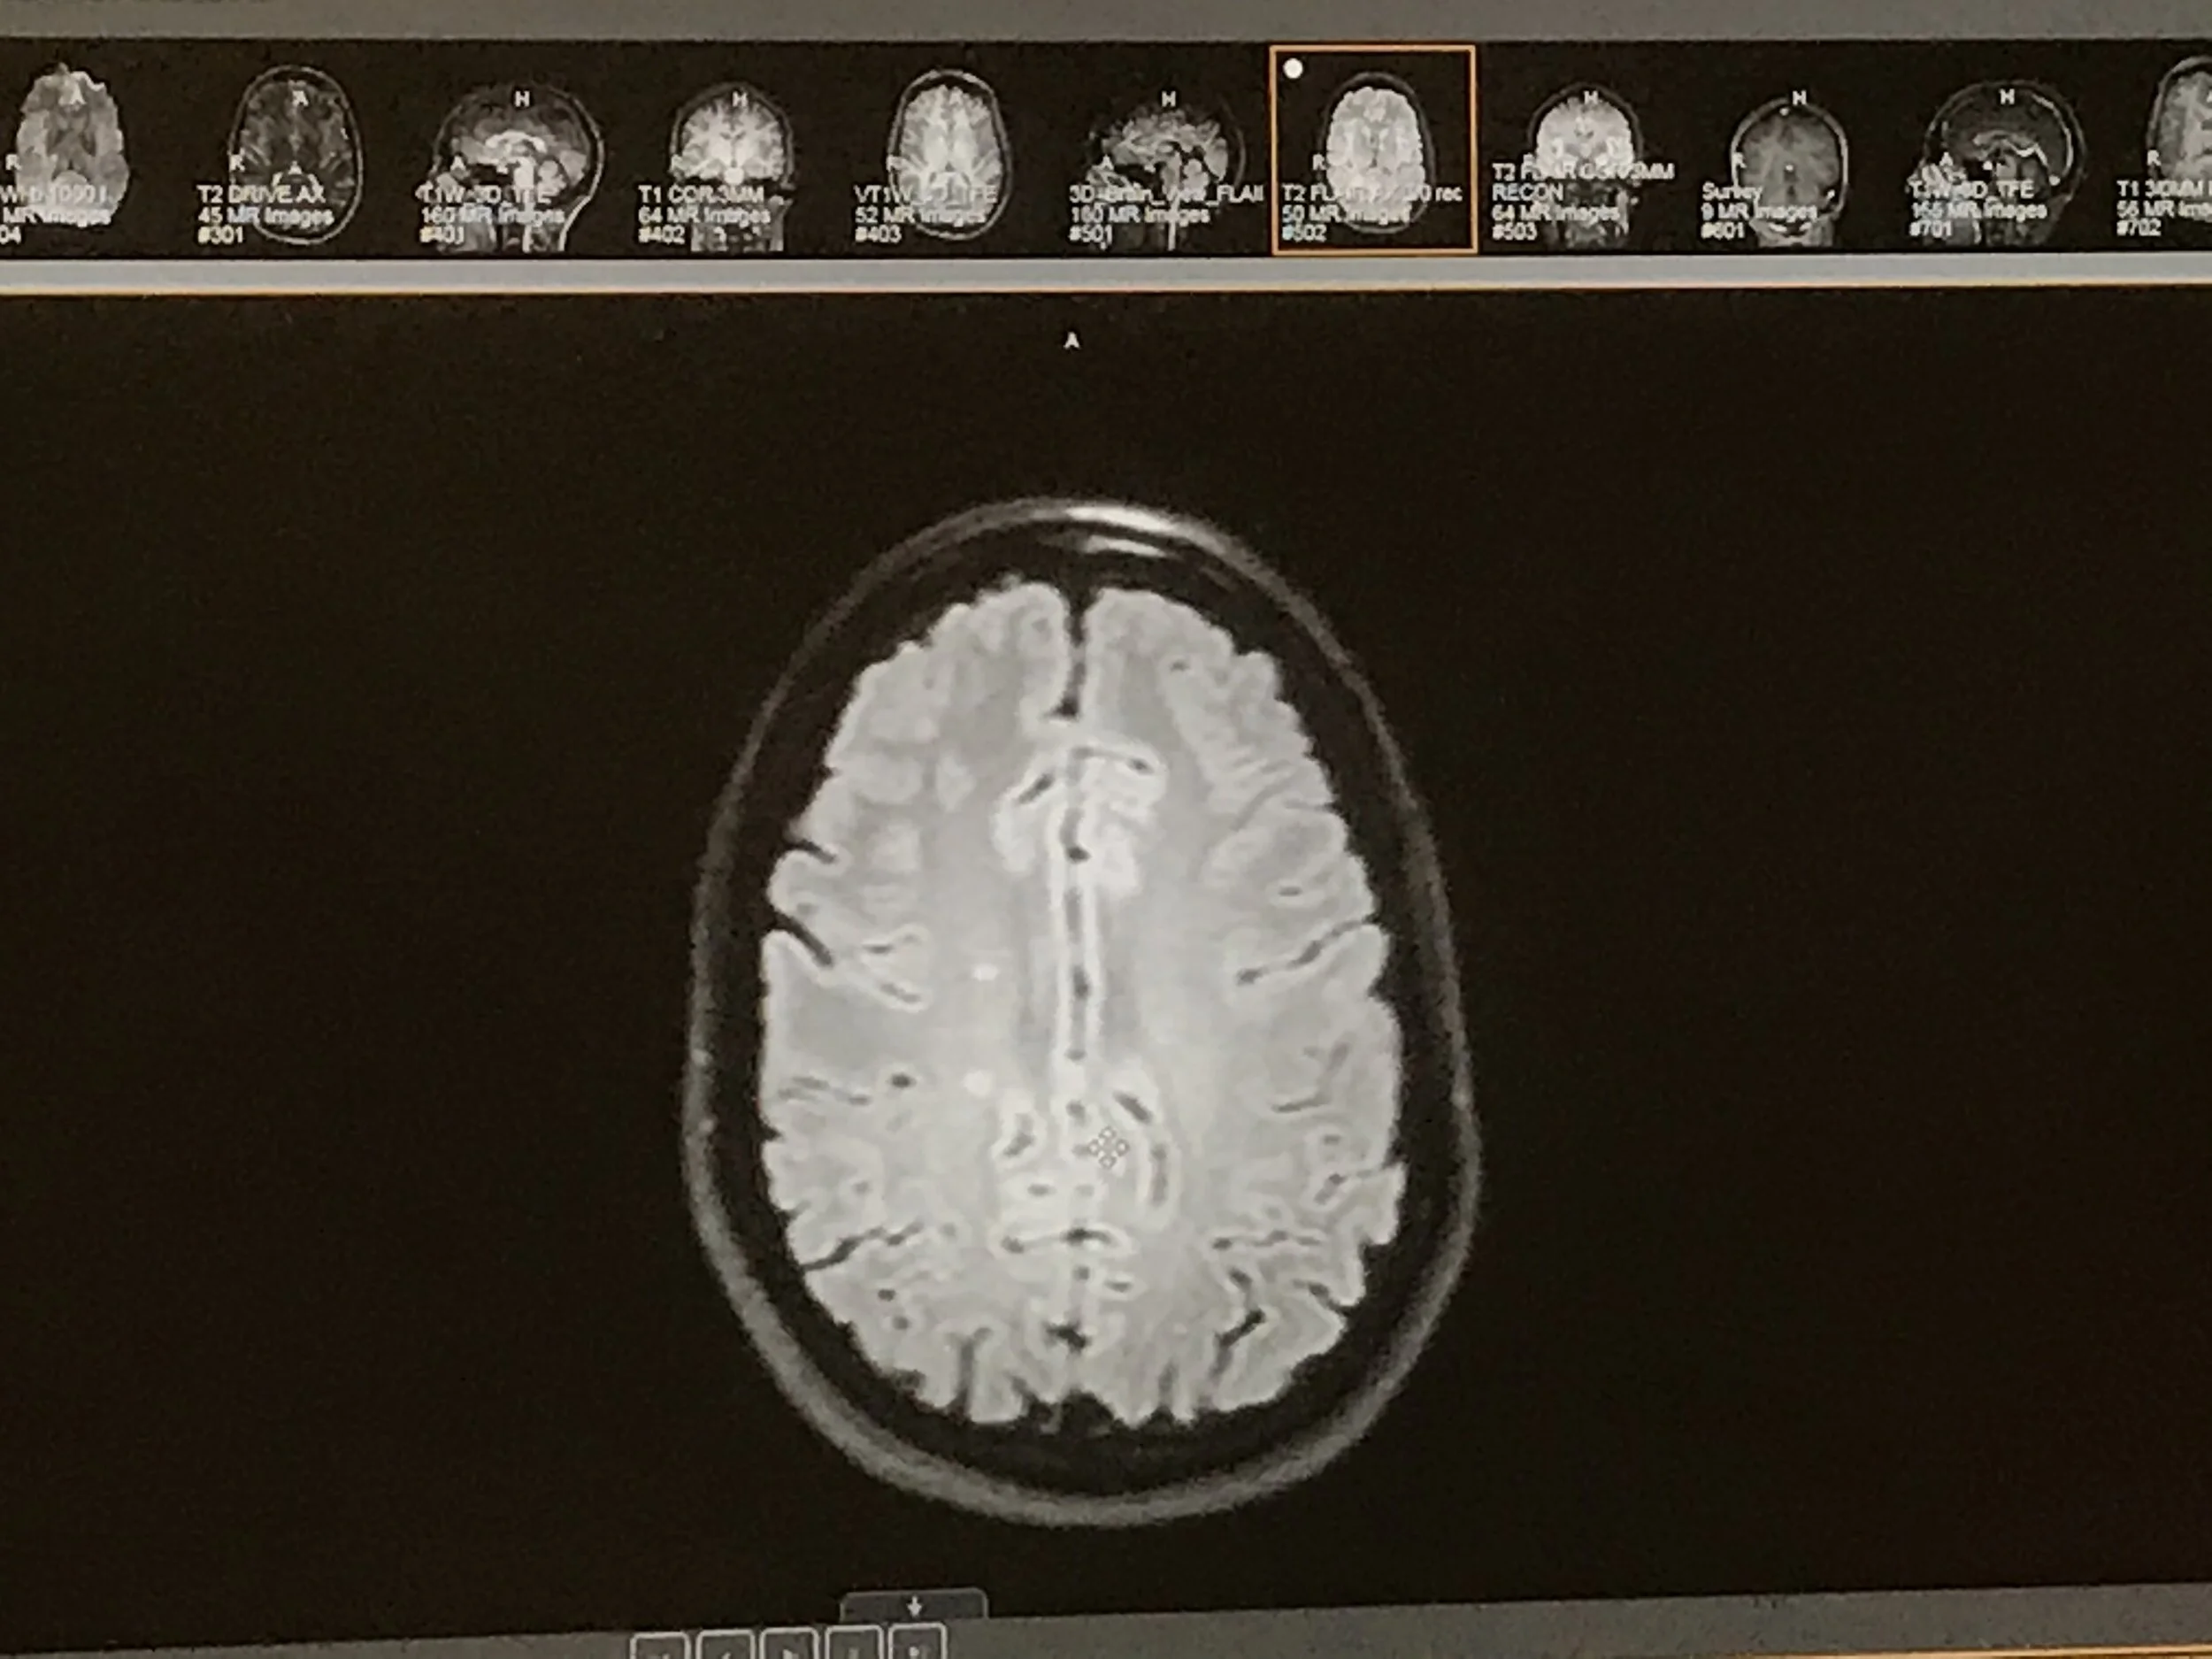

July 2019 Brian.jpg

July 2019 Brain

The is the same look at a lesion, just at different layers within the brain tissue. The left picture is more the more topical of the two, and the picture on the right is a “deeper” look inside my brain, if you will. The fact that the lesion is present deeper in the brain tissue means it had the potential to cause more issues.